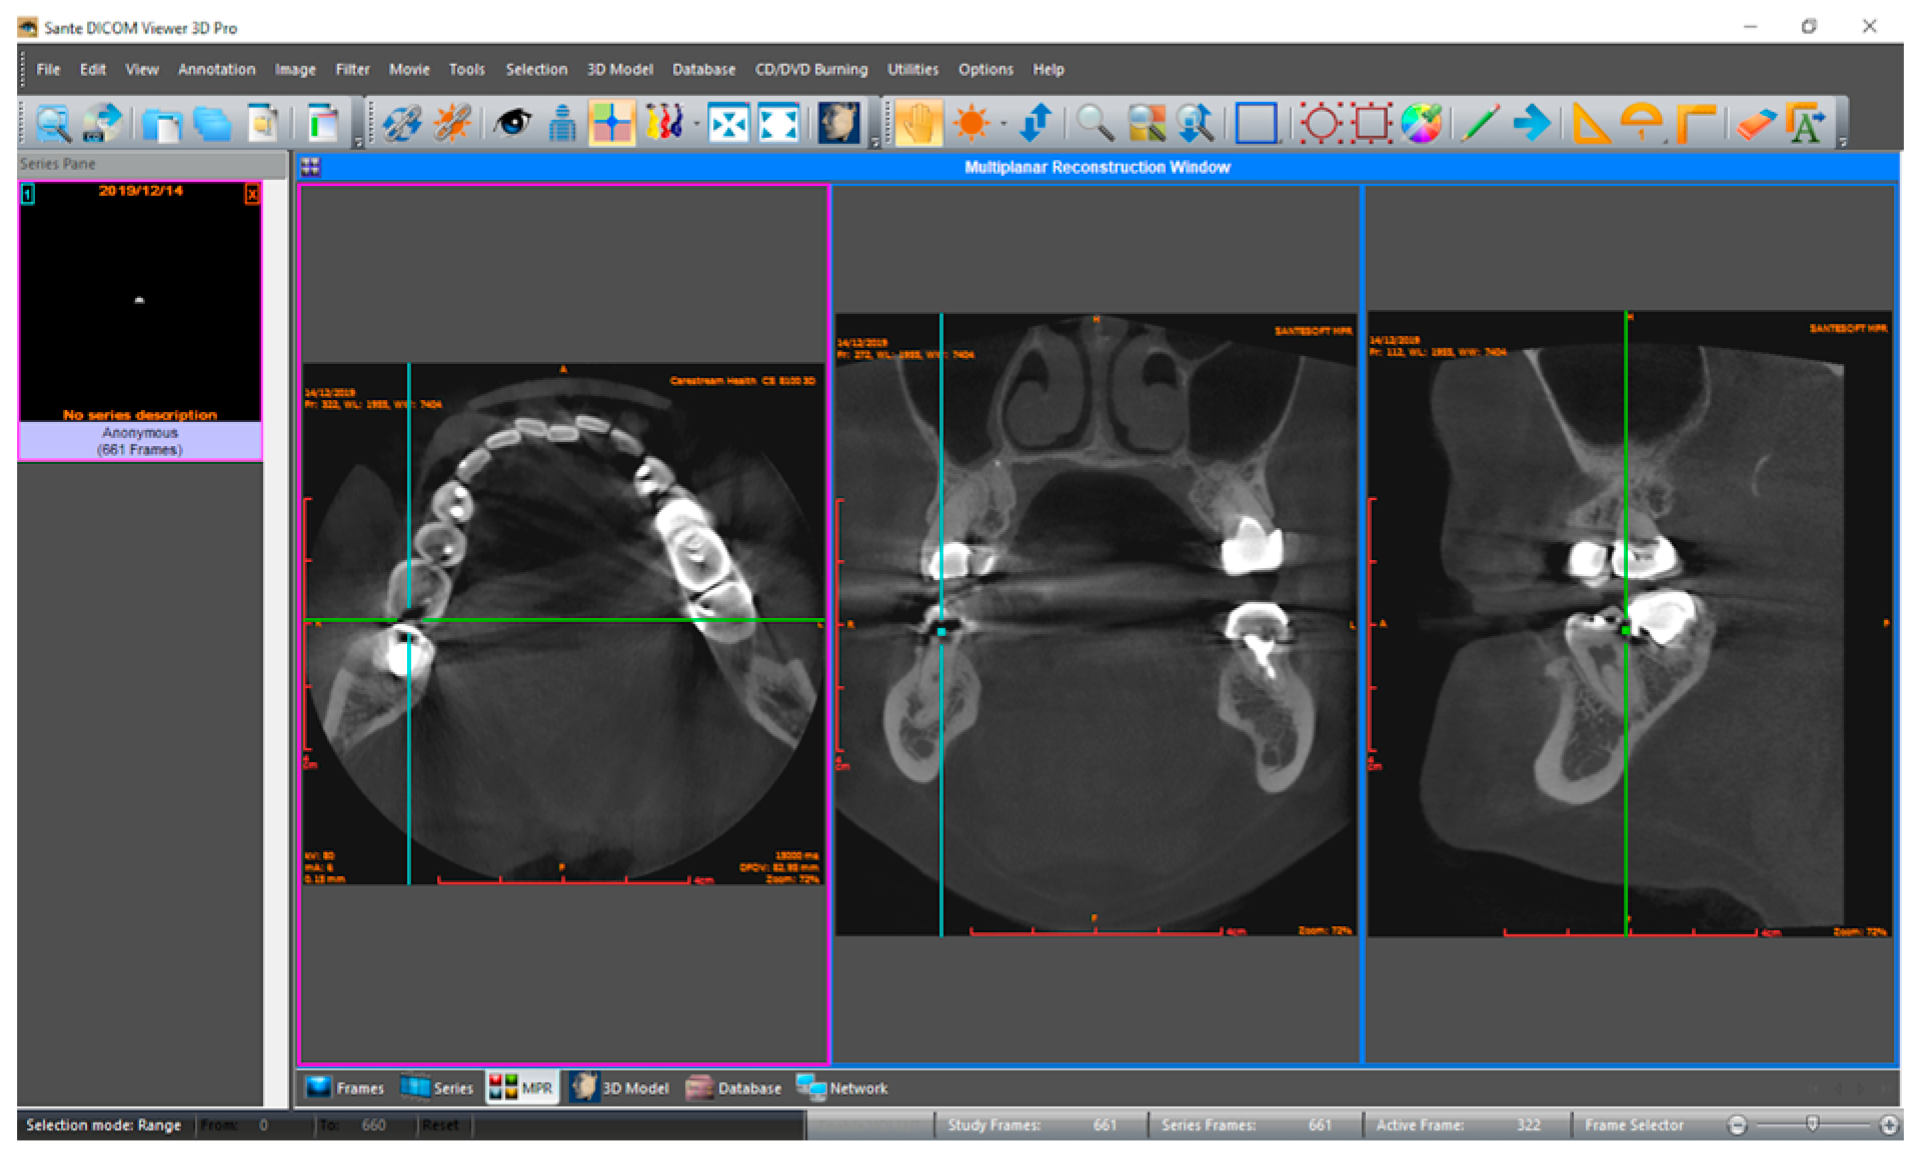

Three observers in dentomaxillofacial radiology evaluated CBCT volumes for dental caries signs, without and with the Diagnocat system. An online conference was conducted prior to evaluations for the calibration of the observers with different levels of experience. The results of aided and unaided evaluations were collected in a template document to ensure standardization among observers. The template with dedicated columns for ‘tooth condition’, ‘mesial surface’, and ‘distal surface’ for each tooth was prepared to collect the responses in an organized manner. Tooth conditions were saved as ‘intact’, ‘missing’, ‘restorated’, ‘support’ and ‘excluded’. Mesial and distal surfaces of the tooth were scored by independent observers separately for the presence of caries on a five-point confidence scale: (1) caries definitely absent, (2) caries probably absent, (3) unsure, (4) caries probably present, and (5) caries definitely present. Primarily, the dataset was imported to Sante DICOM Viewer Pro (Santesoft Ltd., Nicosia, Cyprus) by each observer independently (version 11.6.2 for Windows, 2.0.1 for macOS), and unaided evaluations were performed without any restriction and saved (Figure 1). After a month-long time interval, the dataset was uploaded to the Diagnocat system, and CBCT volumes were analyzed to generate a radiological report. Observers were granted access to the web-based system (Figure 2) to re-evaluate the samples with the aid of the Diagnocat system, and the results were saved using new duplicates of the template.

Figure 1.

Interface for unaided evaluations in the multiplanar reconstruction view (Sante DICOM Viewer Pro for macOS). In multiplanar (MPR) reconstruction mode, the purple frame indicates the active plane (axial in this case), while the blue frames represent other dimensions which follow the actions in the active plane. The green lines represent the intersection point in all three planes, which demonstrate an approximal dental caries in the distal surface of the tooth number 36. Thus, findings in the active frame are evaluated together with other axes.